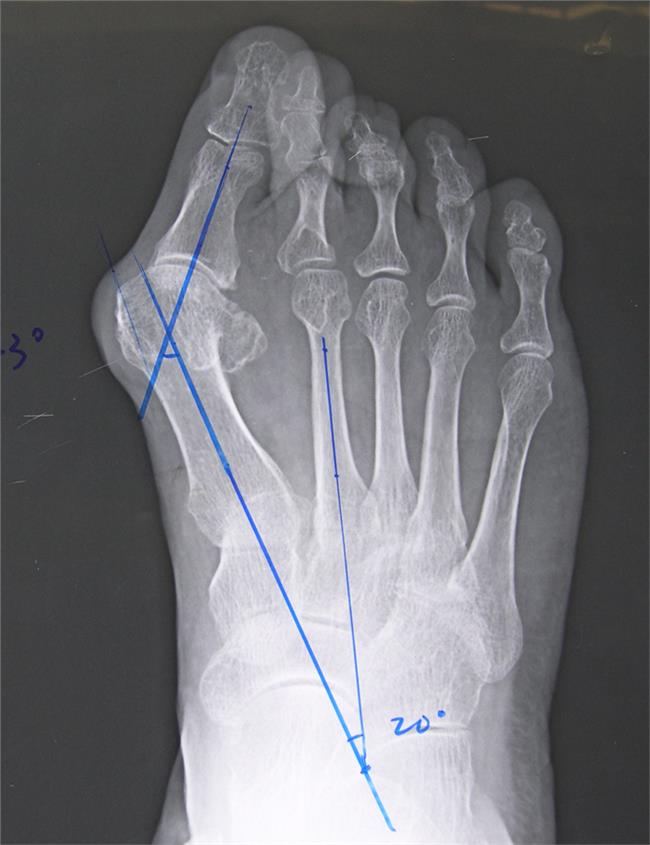

拇趾外翻(hallux valgus)是一种常见的足部疾病,它是指第一跖骨内翻(第一与第二跖骨间夹角大于10度)、拇趾过度倾斜向外侧(外翻角大于15度)的一种畸形。常伴有进行性的第一跖趾关节半脱位。通俗点说拇趾外翻就是指拇趾基底部关节出现一个骨性突起。发生拇外翻时拇趾会偏向第二趾。

拇趾外翻的诊断从外形上就可以进行初步诊断,如果需要进一步了解病情,就需要细致的查体和X线检查,也能为术前计划准备资料。

2. X线检查:应在负重位拍摄足的正侧位片,测出拇趾外翻角度及第一、二跖骨间角,检查第一跖趾关节是否有骨关节炎存在,以及骨关节面的吻合情况。同时还要观察拇趾外翻的内侧隆起程度和籽骨的位置。